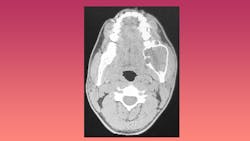

A case was documented at a dental school in which a former dental hygienist, now a second-year dental student, palpated what she perceived to be an anomaly in the mandible of a 68-year-old male. The patient had a history of ameloblastoma in 2013. An ameloblastoma is a benign odontogenic tumor generally present in the jawbone.4 He had been asymptomatic for approximately 2 years.

Presenting in 2019, the student dentist felt that a follow-up CT should be obtained. At that time, it was determined that recurrence was possible, and a series of referrals and images were initiated. By January 2020, a second surgery had been performed and the patient was reported to be doing well. This, and cases similar are the justification for an EO/IO at every visit, as even some benign lesions have the potential to metastasize or redevelop more aggressively.